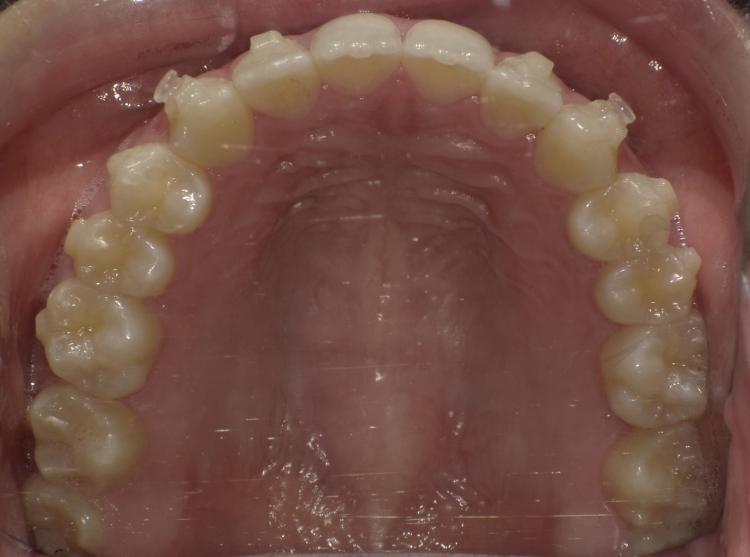

歯を削ってすぐの、マウスピース矯正をはじめた時の写真と現在の写真を比べたものです。

はじめは歯を削った前から4番、5番目の歯の前後の隙間に物が挟まりやすく気になっていましたが、今は歯列が整い隙間も均等になってきました。最終的にどうなるか楽しみです。